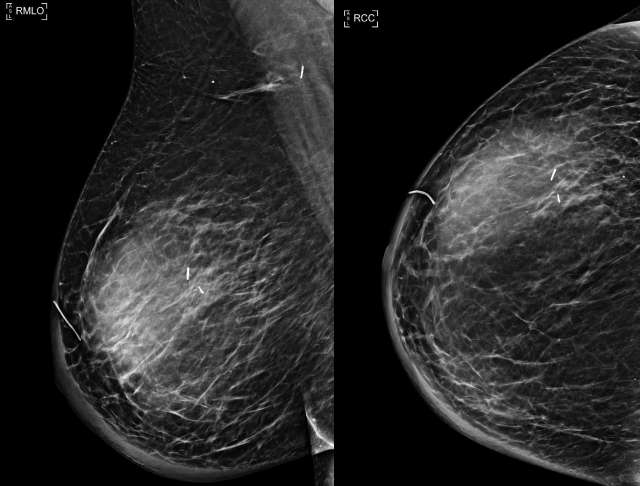

• US: Complicated hypoechoic or isoechoic fluid collection. Mobile debris within the fluid collection and hypervascularity of the adjacent breast tissue are characteristic, Figure 1.7

Case: Post-Surgical Fluid Collections Figure 1

Figure 1 - Ultrasound demonstrates septated, heterogenous fluid collection with surrounding hypervascularity. The patient was 3 weeks status post mastectomy and presented with breast redness and tenderness. The collection was drained, with cultures growing staph aureus.